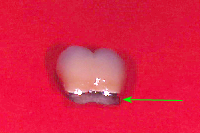

Im Röntgenbild von Abb. 3 ist ein gut erbsengrosses Granulom (Pfeil) an der Wurzelspitze eines toten, devitalen Zahnes feststellbar. Die Patientin wünschte die Erhaltung des Zahnes, zumal auch der vordere Nachbarzahn marktot und beherdet war. Abb. 4 zeigt das Röntgenbild nach der Wurzelfüllung.